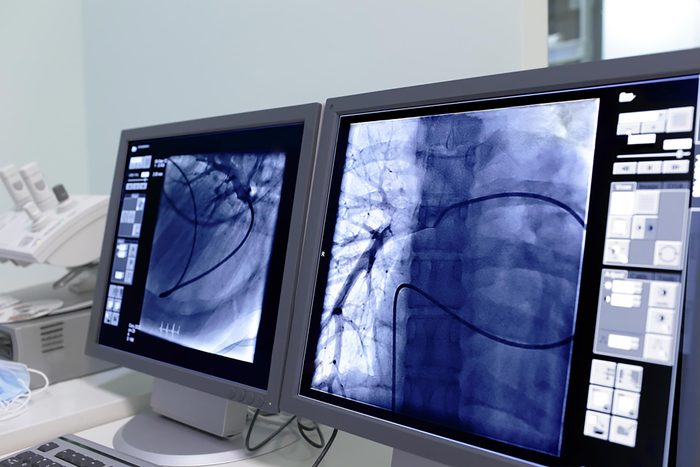

If your doctor suspects you may be at risk for developing heart disease, they might perform a coronary calcium scan. This low-radiation CT scan reveals the amount of calcium built up in your coronary arteries. “When we see calcium in the coronaries, it means that there’s some degree of atherosclerosis—sludge in the pipes that supply the coronaries,” Dr. Freeman says.

In general, lower levels of calcium in the arteries are linked with better heart health, he says, while high levels may indicate an increased risk of heart attack or other cardiovascular events. People with high cholesterol, high blood pressure, a family history of early heart disease, or other traditional heart disease risks may need to undergo the scan more frequently. Dr. Freeman also warns that men, especially those over the age of 70, are more likely to experience coronary calcium buildup.